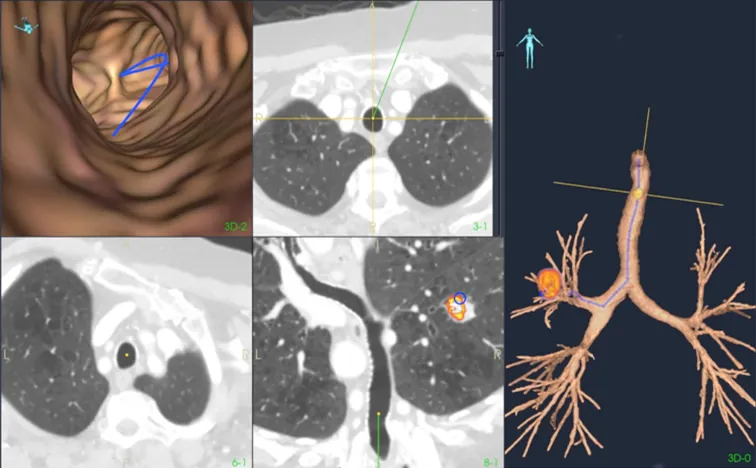

Lunge og bronkoskopi

Lungekreft er den kreftformen med høyest forekomst og dødelighet både i Norge og internasjonalt. Tidlig og presis diagnostikk er avgjørende for overlevelse. Tradisjonelt brukes fleksible videobronkoskop til visuell undersøkelse og biopsi, men metoden har begrensninger når svulster sitter perifert i lungene og ikke er synlige i luftveiene. For å møte denne utfordringen forsker MiDT på avanserte navigasjonsteknologier som kombinerer preoperative CT-bilder med sanntids elektromagnetisk posisjonssporing under bronkoskopi. Dette gir bedre tilgang til små og vanskelig tilgjengelige lesjoner, og kan øke treffsikkerheten ved prøvetaking og behandling. Prosjektene utvikles i tett samarbeid mellom klinikere, teknologer og industripartnere, med mål om å redusere risiko, forbedre pasientbehandling og legge grunnlag for mer persontilpasset diagnostikk.